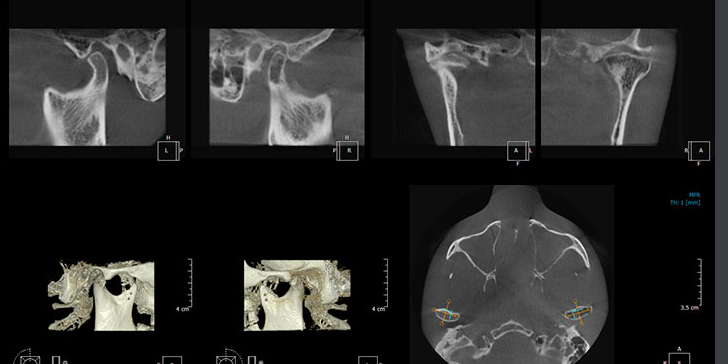

More detail, more confidence

70μm resolution @ 4x3cm

Image reconstruction in 6 seconds

Superior image processing technology

Various options

One shot Ceph & Scanning ceph

Object scan, a new feature for digital impression

Scan your model/impression and Convert the DICOM to STL